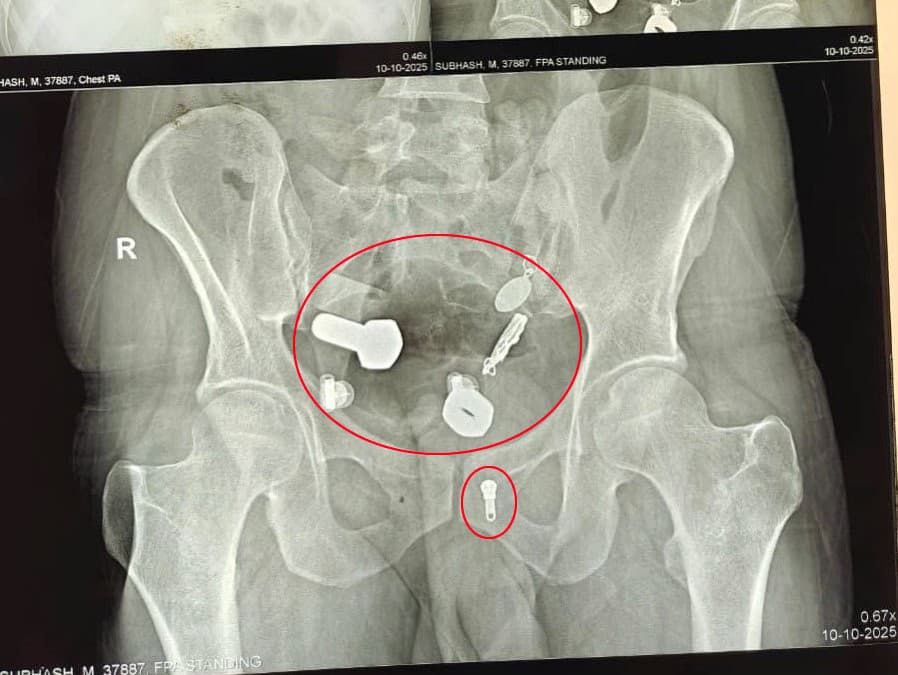

Lekári najskôr urobili röntgen a CT vyšetrenie, ktoré odhalilo, že v pažeráku pacienta uviazli náramkové hodinky, zatiaľ čo v čreve sa nachádzali kovové fragmenty, matice a skrutky. „Niečo také sme ešte nevideli,“ uviedol jeden z členov operačného tímu pre Need To Know.

Predmety – vrátane hodiniek – chirurgovia vybrali cez malý rez v brušnej dutine. Na záberoch z operačnej sály je vidieť, ako lekári postupne vyťahujú lesklé kovové kúsky pokryté žalúdočným obsahom.